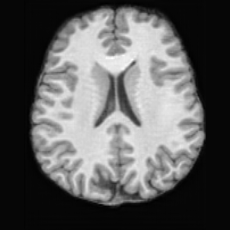

(a)PathologicalInput ImageSynthSR [18]Brain-ID [28]UNA [30]USBHealthyGround TruthRefer to captionRefer to captionRefer to captionRefer to captionRefer to captionRefer to captionRefer to captionRefer to captionRefer to captionRefer to captionRefer to captionRefer to captionRefer to captionRefer to captionRefer to captionRefer to captionRefer to captionRefer to captionRefer to captionRefer to captionRefer to captionRefer to captionRefer to captionRefer to caption(b)HealthyInput ImageConditionalLesion MaskUNA [30]USBRefer to captionRefer to captionRefer to captionRefer to captionRefer to captionRefer to captionRefer to captionRefer to captionRefer to captionRefer to captionRefer to captionRefer to captionRefer to captionRefer to captionRefer to captionRefer to caption

Figure 5: Comparison of bidirectional brain editing. (a) pathology-to-healthy, the circles and arrows highlight lesion regions and unsuccessful reconstructions; (b) healthy-to-pathology. Note that SynthSR and Brain-ID cannot perform healthy-to-pathology editing.

Healthy-to-Pathology Editing. As shown in Fig. 5 (b), given a healthy brain image paired with a random lesion mask, USB seamlessly embeds the lesion into the healthy anatomy, producing realistic pathological appearances consistent with surrounding structural context. Yet UNA’s syntheses are visually unrealistic, with the conditioned lesion mask simply overlaid as a parallel layer onto the healthy brain. Tab. 3 further demonstrates USB’s superior performance. The evaluation was conducted on 100 pairs of lesion masks and healthy brains, with real stroke images